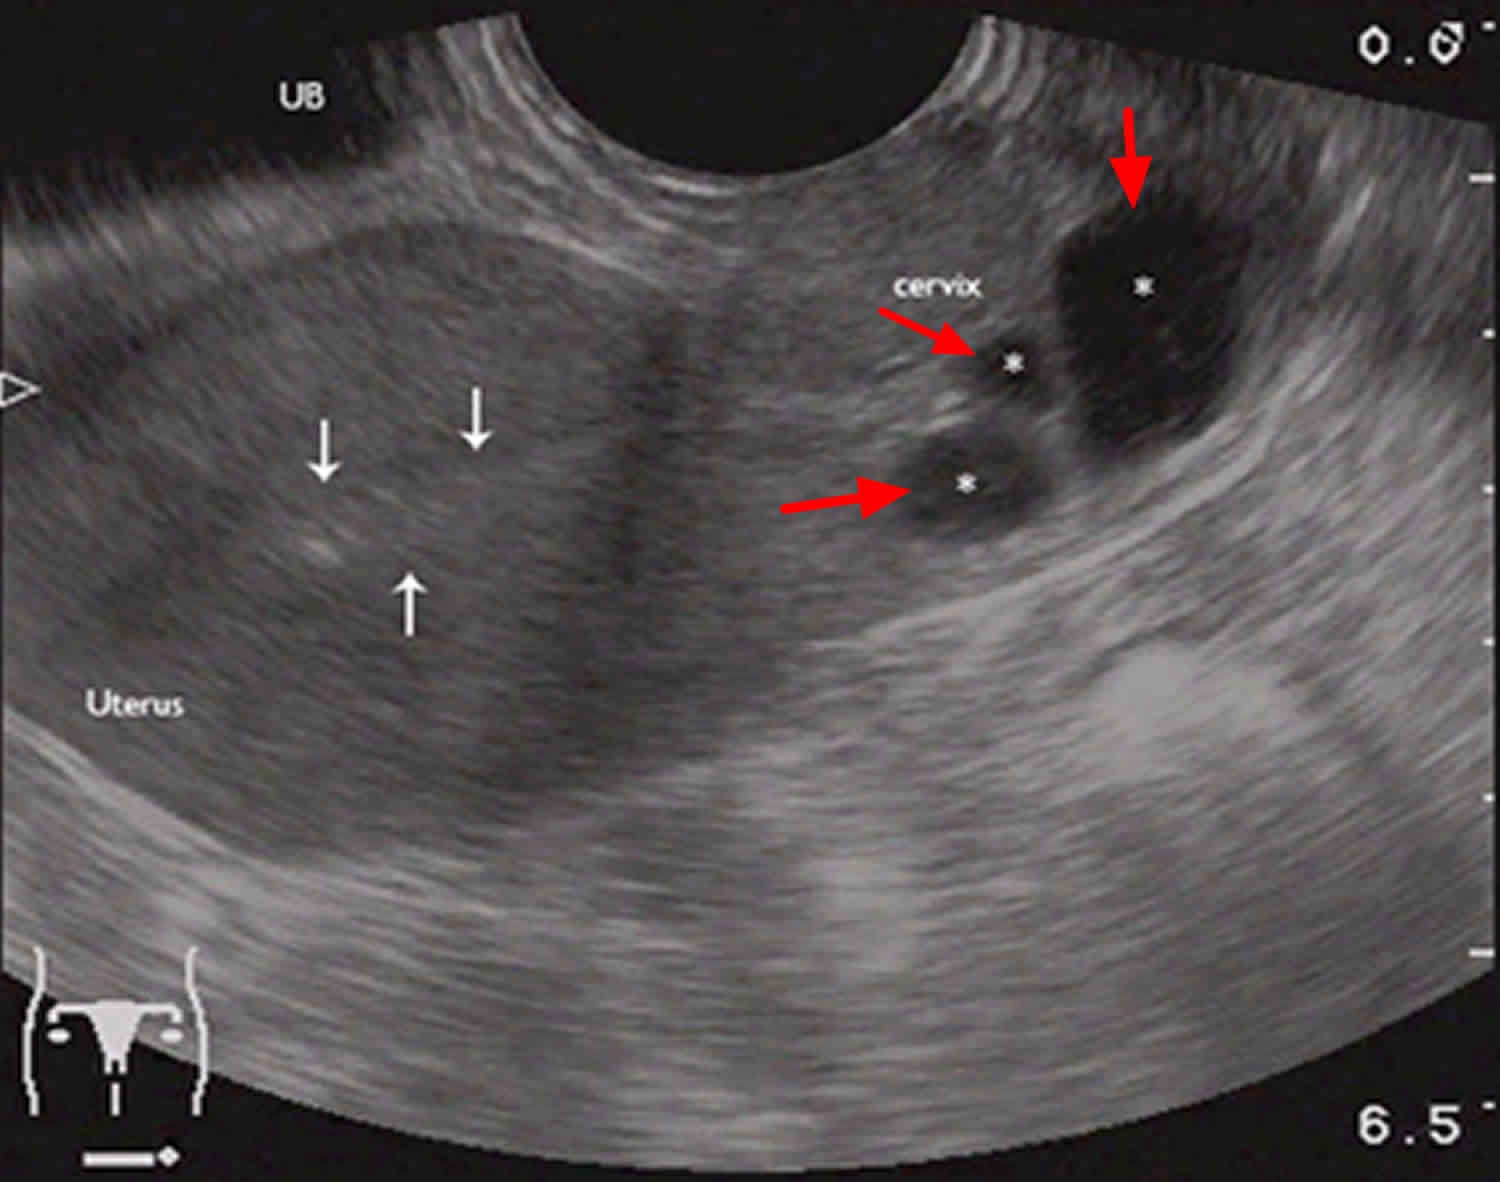

Nabothian cysts/cystic cervicitis/ adenoma malignum Radiology, Radiology imaging, Obstetrics

Mulher com 44 anos de idade com quistos de Naboth. a) No plano sagital… Download Scientific